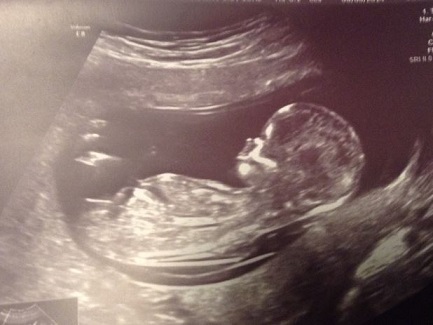

I went to my ultrasound yesterday and I DID spotted a girl nub but my ultrasound lady did not want to say anything since she told me this was too early to tell. Please help me out . thanks everyoneAttachment 20241Attachment 20242

looks girly :)

Girl. I'd bet my morning coffee on it ;) And that is serious stuff.

Definitely girl

girl

Pink